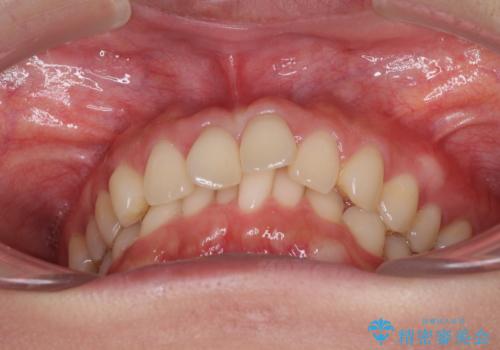

インビザラインによるディープバイトの改善

- 口元の前突感と深い咬み合わせ(ディープバイト)を気にして来院された患者様です。

インビザラインによる上下歯列の遠心移動(後方移動)と、それに伴う近心傾斜(前方傾斜)の改善により、口元の突出感とディープバイトを改善することとしました。

前歯のデコボコを最も気にしていましたが、咬み合わせが深く歯ぎしりが自由にできない点を指摘すると、常に食いしばってしまうことも悩みであることが分かりました。